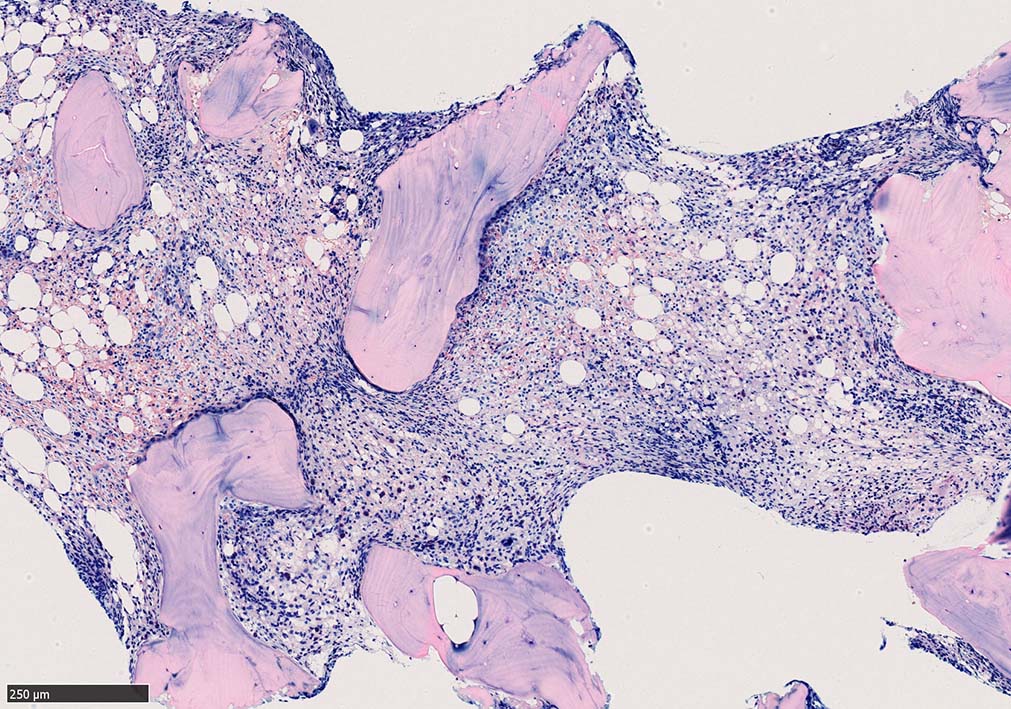

骨髄生検

bone marrow trephine biopsy: dry tapのため骨髄生検が行われる. cellularityは40-80%とhypercellular marrow. 流れのある細胞配列は線維化を疑わせる.

ASD-G 低倍率所見では赤芽球血島は幼若赤芽球の集簇巣が散在する, 顆粒球系細胞(ASDに赤く染色される)は減少,granulopoietic hypoplasiaを呈する.疎な集簇を示すmast cellsの増加がある.

ASD-G陰性の細胞がびまん性に増加しているように見える.

Ag染色では, 疎な弾性線維が増生し,増殖細胞を小胞巣状に分画するいわゆる「lymphomatoid pattern」を呈する. 本例では, Mgkに異形成所見がある.